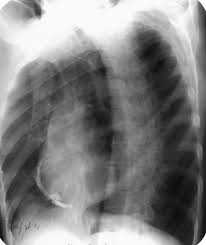

- 호흡 곤란: 심낭 주위의 염증으로 인해 심장의 움직임이 제한되거나 심낭액이 증가할 경우, 호흡이 어려울 수 있습니다. 특히 심낭액이 증가하면 폐의 움직임을 방해할 수 있습니다.

2. 심낭액 배출 시술

- 심낭액이 과도하게 증가하여 호흡이나 심장 기능에 영향을 미치는 경우, 심낭액을 배출하는 시술을 고려할 수 있습니다. 이는 심낭액의 압력을 줄여 호흡과 심장 기능을 개선하는데 도움을 줄 수 있습니다.